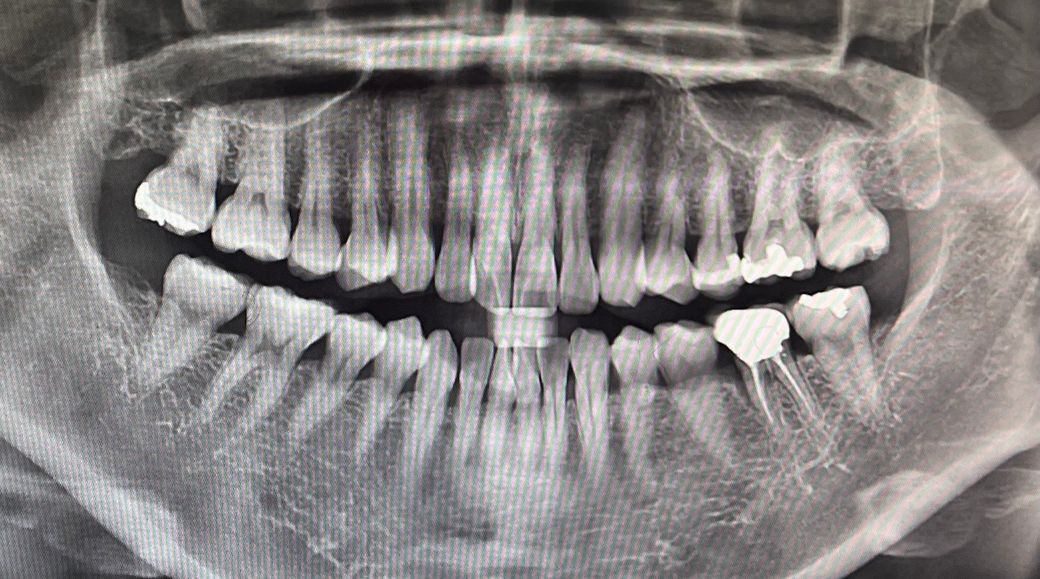

크라운이후 사진

상악동염은 파노라마 사진상에서는 관찰되지 않는 듯 합니다. 신경치료를 했던 곳에서 다시 평가 받아보셔야겠습니다.

사진상으로는 상악동에 염증이 있거나 그래 보이진 않습니다. 보철문제인거 같으니 보철을 봐주는 대학병원 보철과를 한번 가보세요.

파노라마 사진상 상악동이 지저분해 보이거나 염증양상은 아닙니다.